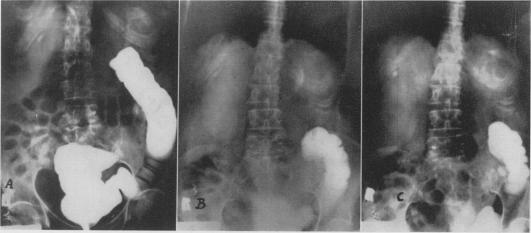

Ureterosigmoidostomy; experience with the Goodwin procedure.

Ann Surg. 1956 Mar;143(3):337-48. doi: 10.1097/00000658-195603000-00006.